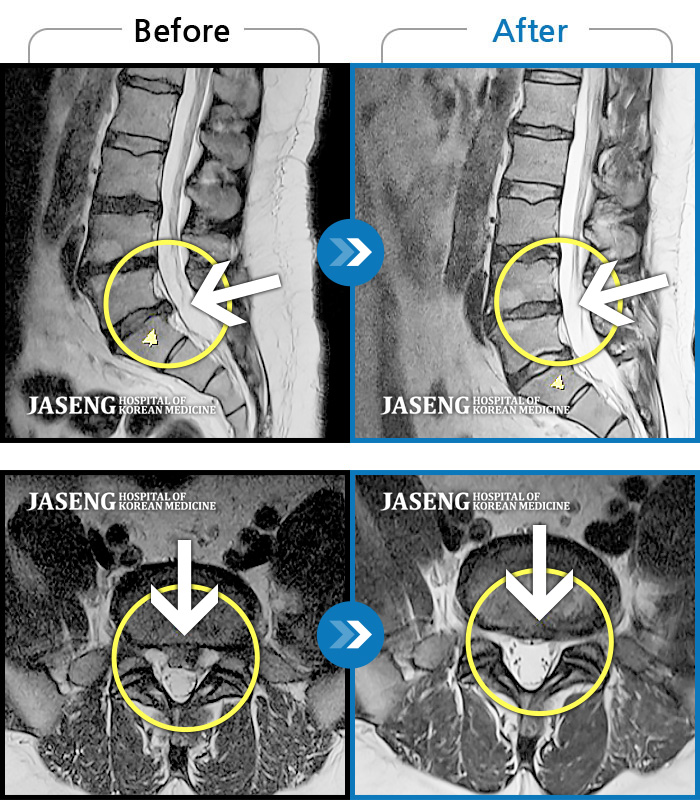

허리디스크

도움받은 사례

광주 · 장영우 원장

양측 허리 통증과 좌측 허벅지부터 발바닥까지 송곳으로 찌르는 듯한 통증 지속되어 내원하셨습니다.

촬영시기

2023.12.26 ~ 2024.12.05

2024.12.12

조회수 494